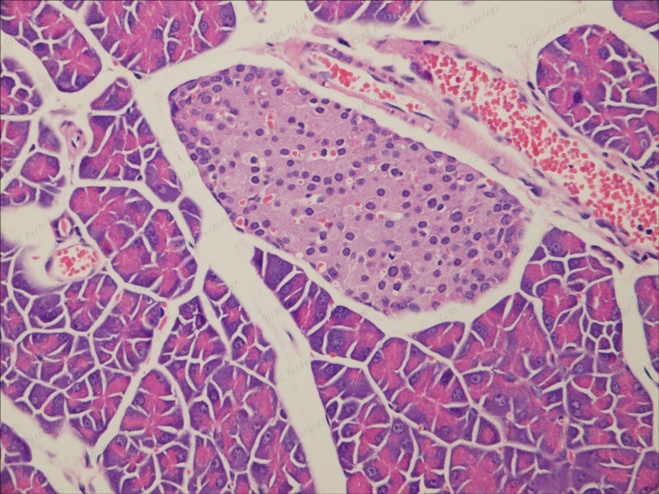

胰腺胰島40